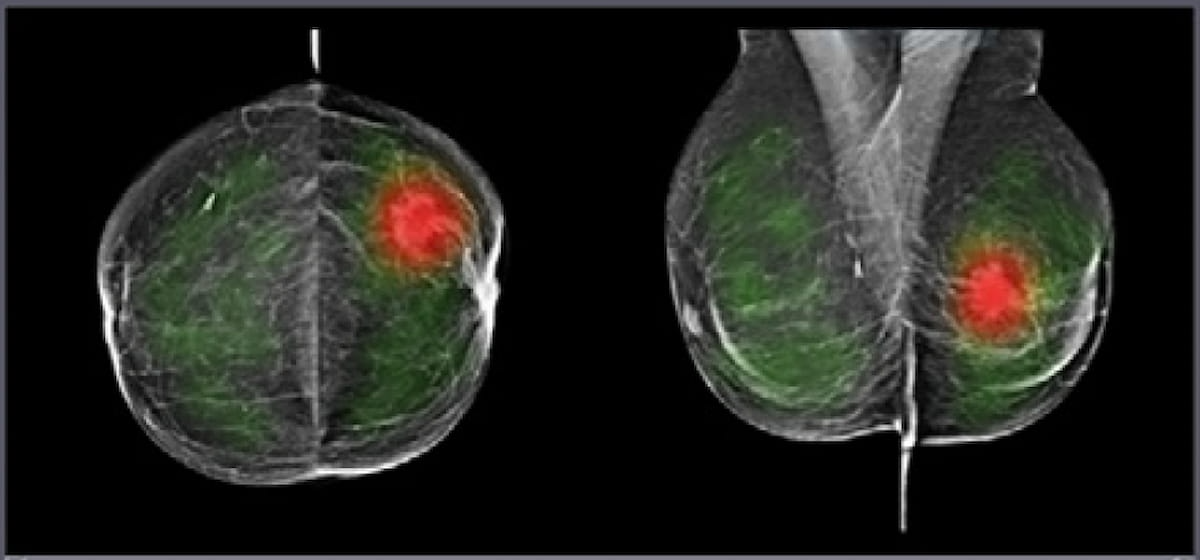

Comparing year-long findings with and without adjunctive artificial intelligence (AI) at a breast cancer screening program in Spain, researchers found the combination of digital breast tomosynthesis and AI had a 92.5 percent accuracy for diagnosing cancer in patients with elevated risk.